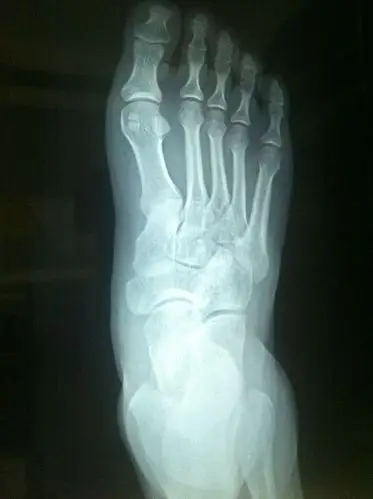

拍片前,满脑子都祈祷不是骨折,只是崴脚或者韧带受伤.

医生好崴脚了一周后的片子崴脚一周后石膏固定请医生给个

打球崴脚了 麻烦看一下x片

打篮球崴脚了